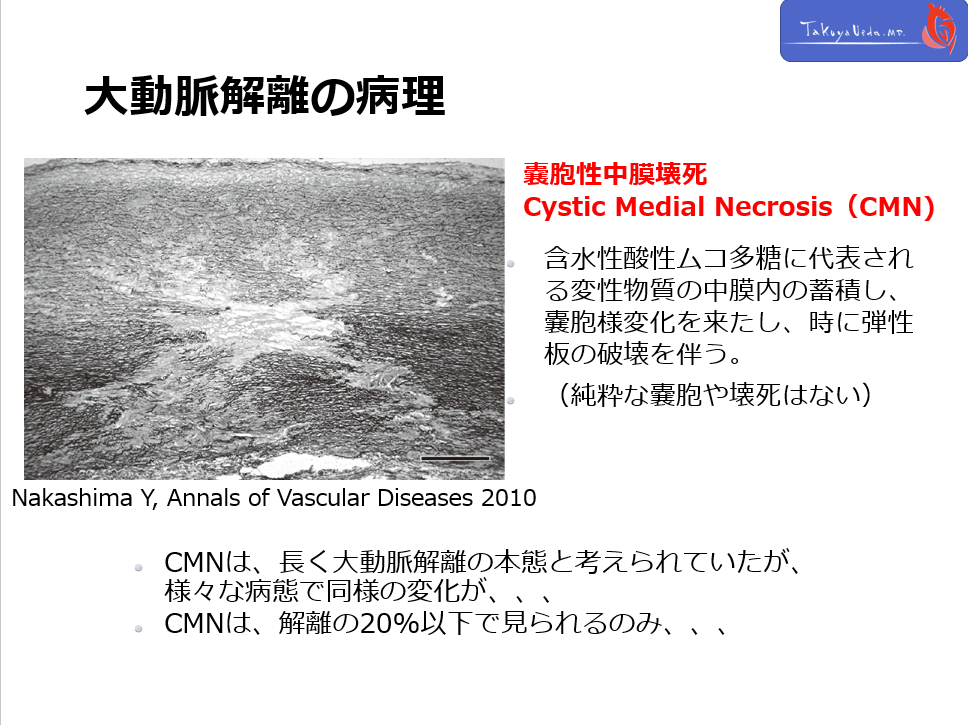

これらの患者に共通して見られるのは、cystic medial necrosisという病理学的変化です。

Fig. 1 Cystic medial necrosis observed in a patient with aortic dissection.

There was a focal loss of elastic fibers in the aortic media, accompanied by a decrease in smooth muscle cells and an increase in proteoglycans (Elastica van Gieson stain). Scale bar = 500 μm (Reproduced from Ref. 12).